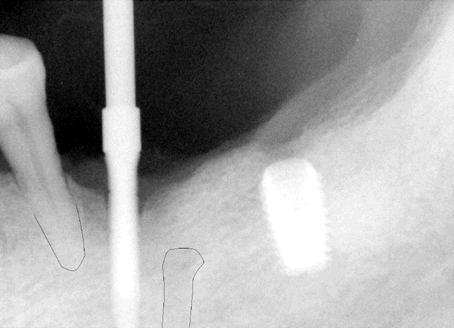

Fig.8 (left) and 9 (right) After initial

osteotomy, paralleling pins were inserted at 6 mm (Fig.8) and 8 mm

(Fig.9) for X-ray. The surgeon did not find the mental nerve relative

to the pins. He paid attention to changing the projectory of the pins/osteotomy

(compare Fig.8 vs. 9). The surgeon did not expose the mental nerve on

the left side.

As mentioned above, local infiltration was used during lower right implant placement. In case the neural bundle is invaded, we may notice it earlier. The drawback is that the depth of anesthesia cannot be maintained for long. You have to re-inject frequently. When working on the lower left quadrant, inferior alveolar block was used from the beginning with local infiltration for hemostasis. More importantly the mental nerve was not dissected for orientation purpose. |